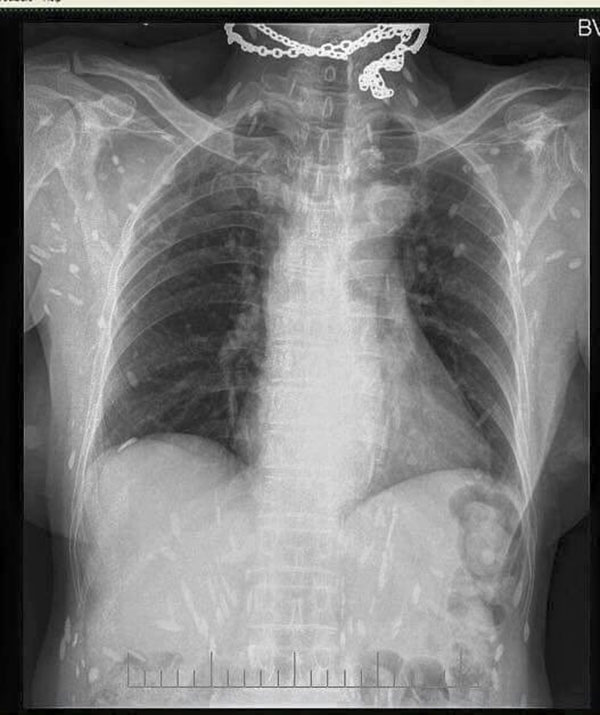

Nếu nhìn hình ảnh chụp phim X-quang của người bị "bệnh gạo" sẽ thấy "gạo" chi chít, rải rác khắp nơi.